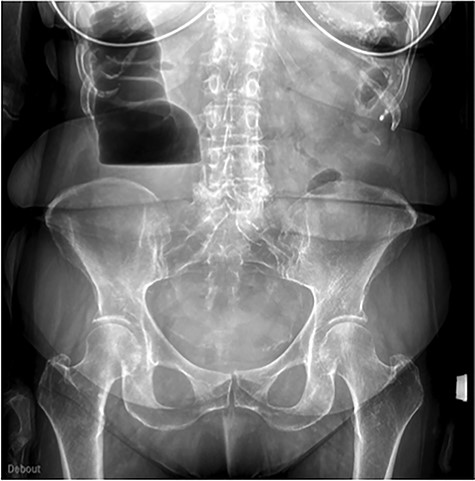

An abdominal radiography showed hydro-aeric levels and dilatation of the intestinal bowel (Fig. 1).